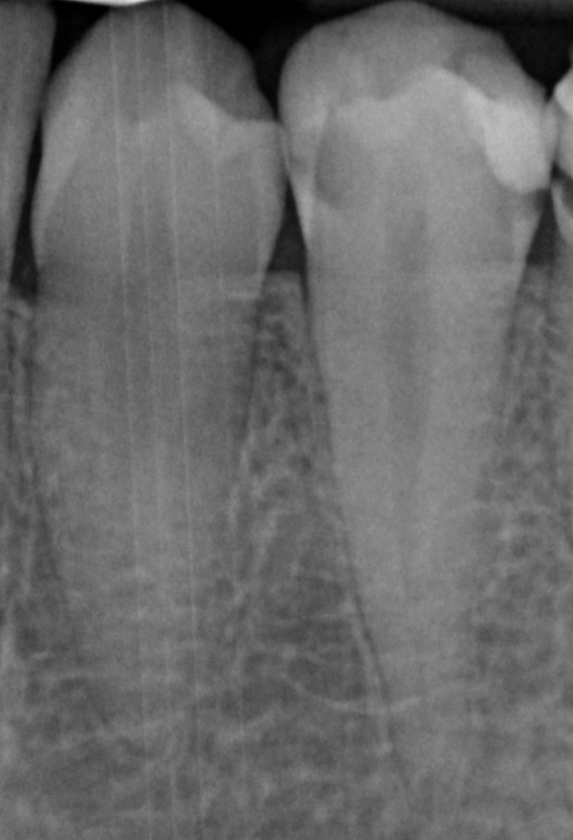

De cursus bestaat uit een combinatie van interactieve theorie en praktische oefeningen. Er wordt gewerkt met preparatiemodellen waarin een diepe caviteit en pulpablootstelling wordt gesimuleerd.

• Preparatie van diepe caviteiten in molaren;

• De anatomie van het pulpadak en pulpakamer correct te herkennen en prepareren;